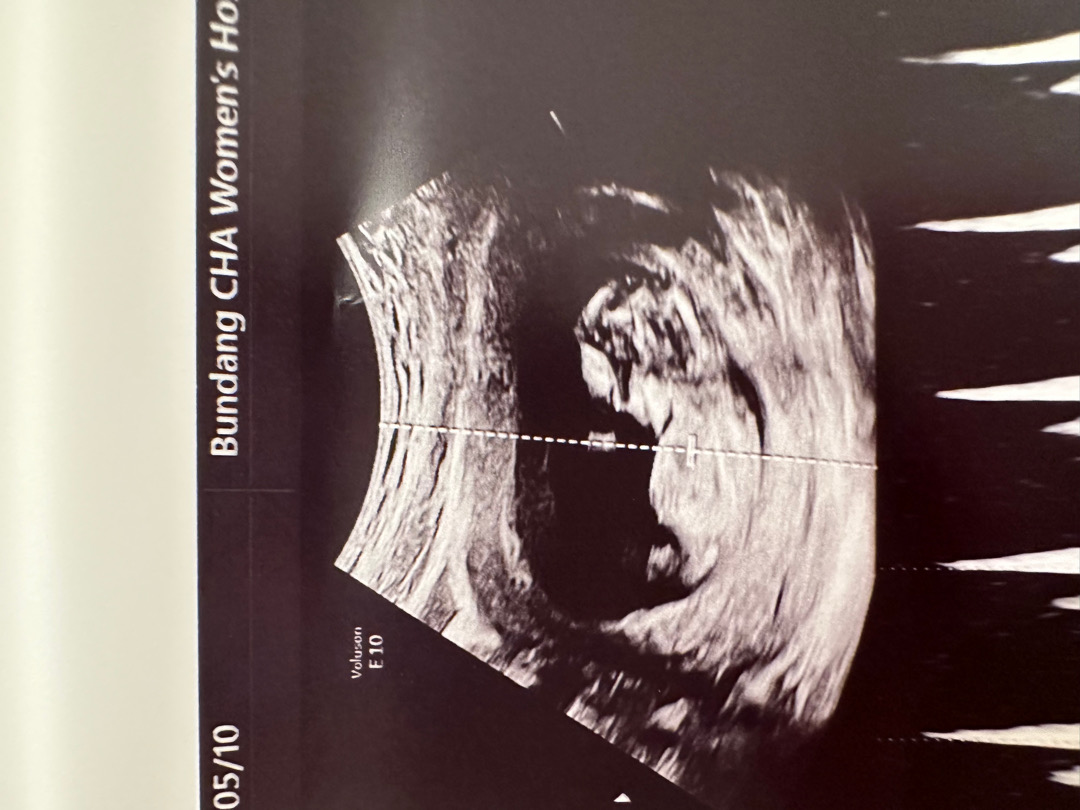

오늘 병원다녀왔어용 12주차!

기형아 검사하고 왔습니다!! 뽀듬이가 다리를 꼬고있어서 성별이 안보이는데 각도법잘아시는분 있으시면 편하게 댓글달아주세용 ㅎㅎ감사합니다

오옷 아들..?애매하네요ㅋㅋ